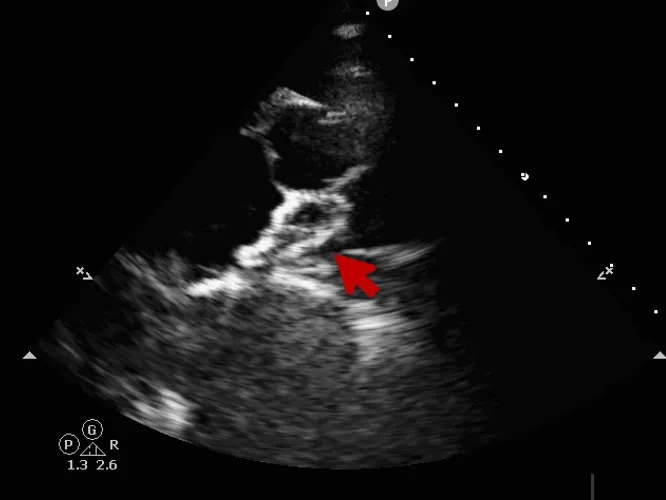

术前超声

超声描述:右房室较大,左房室不大。房间隔中部可见中断,约14x16mm。缺损边缘较硬,二尖瓣侧缘、后上缘分别为16mm、8mm,主动脉侧缘、后壁缘分别为0mm、10.7mm,上、下腔静脉侧缘分别为16、14mm。十字交叉存在。房间隔长度43mm。M型二尖瓣呈双峰,前后叶逆向,E-E间距相等。

术中复测

超声可见房间隔连续中断,彩色多普勒可见过隔血流

测量房间隔缺损直径最大为23.9mm,房间隔总长53.8mm